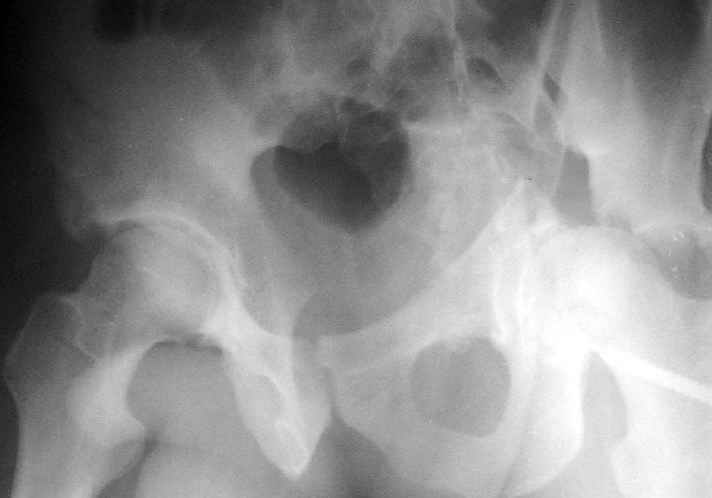

Пациент переведен в нашу клинику на 5 день после множественной травмы 25.01.2003 - двустороннее повреждение вертлужных впадин, разрыв левого крестцово-подвздошного сочленения. Вывихи обоих бедер. В месте первичного поступления подвздошный вывих правого бедра вправлен 26.01.2003, наложено вытяжение за левую вертельную область. Остеосинтез левой вертлужной впадины выполнен у нас 6.02.2003. Вопрос: надо ли синтезировать задне-верхний край правой вертлужной впадины?

правую впадину собрали здорово! Мои поздравления Рункову. Сами меня учили-учили, а где же запирательная проекция левой вертлужной

впадины. Такое впечатление что на КТ есть интерпозиция кусочком, тогда уж точно надо туда залесть, а так, я считаю не стоит.

Уважаемый Алексей, через месяц после повреждения обострять травму, чтобы продлить "колясочный" срок? Второй сустав станет опорным не скоро.Головка на Ртг концентрически вставлена, задний фрагмент не интерпонирует, лимбус,по видимому тоже, ямочный фрагмент мешать не должен,герметизирующую манжету адекватно восстановить, обычно, не удается. Выгоды от оперативного вмешательства сомнительны. Я бы оперировать не стал.Еще месяц без нагрузки (по меньшей мере) и в нашей "конторе"- МОНИКИ(Вы наверняка знаете О.Ш.Буачидзе) положились бы на ощущения пациента при активных движениях правым бедром. Можно и сейчас проверить на возможность блокады и тогда принимать окончательное решение.